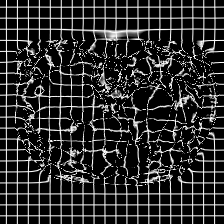

In clinical practice, well-aligned multi-modal images, such as Magnetic Resonance (MR) and Computed Tomography (CT), together can provide complementary information for image-guided therapies. Multi-modal image registration is essential for the accurate alignment of these multi-modal images. However, it remains a very challenging task due to complicated and unknown spatial correspondence between different modalities. In this paper, we propose a novel translation-based unsupervised deformable image registration approach to convert the multi-modal registration problem to a mono-modal one. Specifically, our approach incorporates a discriminator-free translation network to facilitate the training of the registration network and a patchwise contrastive loss to encourage the translation network to preserve object shapes. Furthermore, we propose to replace an adversarial loss, that is widely used in previous multi-modal image registration methods, with a pixel loss in order to integrate the output of translation into the target modality. This leads to an unsupervised method requiring no ground-truth deformation or pairs of aligned images for training. We evaluate four variants of our approach on the public Learn2Reg 2021 datasets \cite{hering2021learn2reg}. The experimental results demonstrate that the proposed architecture achieves state-of-the-art performance. Our code is available at https://github.com/heyblackC/DFMIR.